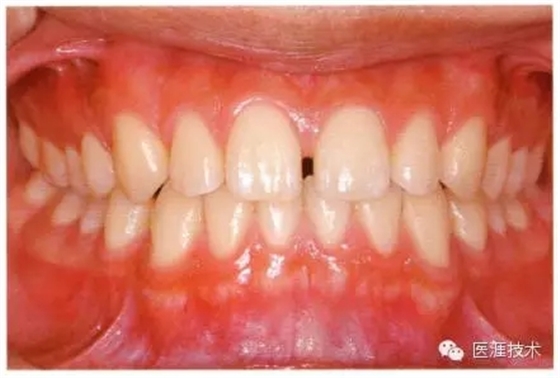

18歲男性的健康口腔內(nèi)部

圖為18歲男性,無特殊全身疾病,不抽煙。持續(xù)保養(yǎng)10年。牙菌斑控制比以前好,因刷牙稍稍過度臉頰側(cè)有牙齦萎縮傾向,但牙齒及牙周組織仍保健康。